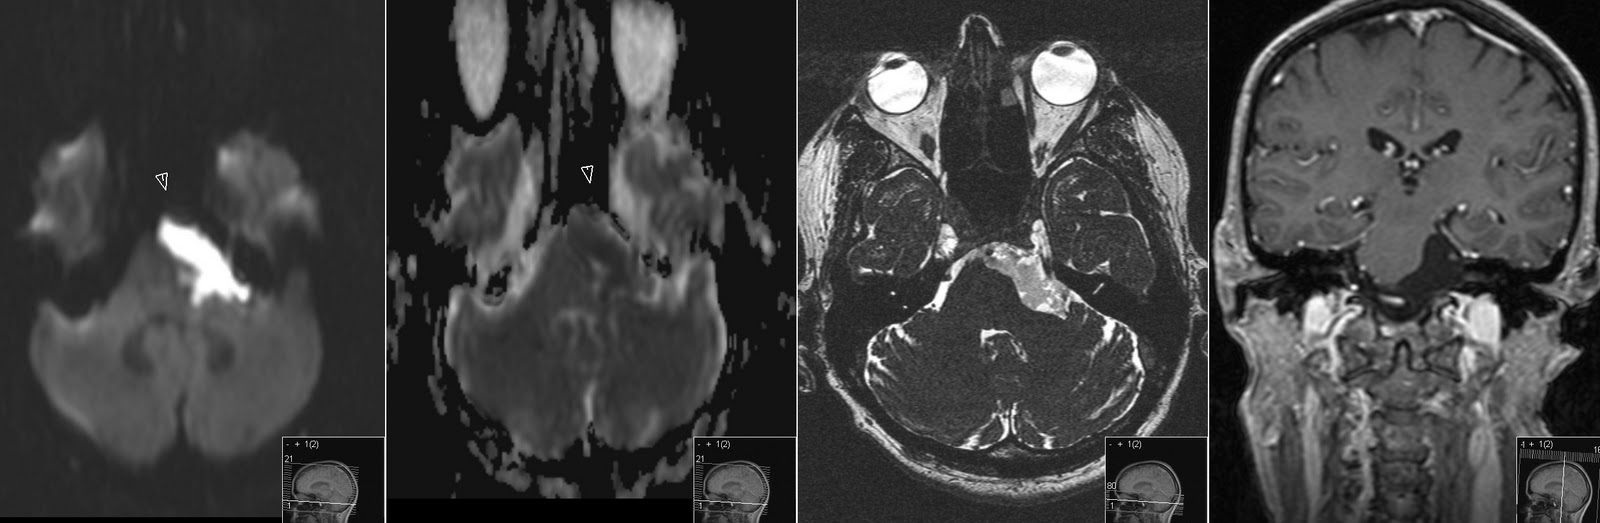

Intracranial epidermoid cyst - Wikipedia, The Free Encyclopedia

Intracranial epidermoid cyst This article has multiple issues. brain stem is composed of 12 pairs of cranial nerves that come out of the brain at the base of the skull and into the spine. Any damage or bruising to the brain stem can result in permanent impairment, such as ... Read Article